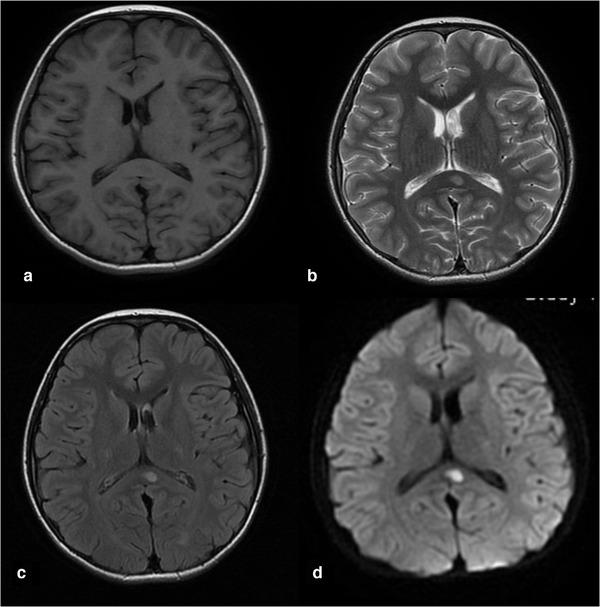

To investigate the clinical features, imaging features, and prognosis of mild encephalitis/encephalopathy with a reversible splenial lesion (MERS) in children METHODS: The clinical and imaging data of a cohort of 28 children diagnosed as MERS from January 2019 to October 2020 were retrospectively analyzed RESULTS: Of the 28 patients, 17 were males and 11 were females. The onset age ranged from 8 months to 12 years old, with an average age of 4 years and 2 months. All children developed normally before onset, and three of them had a history of febrile convulsion. More than half of the patients (62.9%) had preceding infections of gastrointestinal tract. All the cases developed seizures, and most (71.4%) had more than one time. Other neurological symptoms included dizziness/headache, consciousness disorder, limb weakness, blurred vision, and dysarthria. Cranial magnetic resonance imaging (MRI) showed lesions in the splenium of the corpus callosum in all, extending to other areas of the corpus callosum, bilateral semi-ovoid center, and adjacent periventricular in two cases. The clinical symptoms were relieved after steroids, intravenous immunogloblin, and symptomatic treatment, without abnormal neurodevelopment during the followed-up (2 months-2 years). Complete resolution of the lesions was observed 8-60 days after the initial MRI examinations CONCLUSION: MERS in children is related to prodromal infection mostly, with a wide spectrum of neurologic symptoms, characteristic MRI manifestations, and good prognosis.